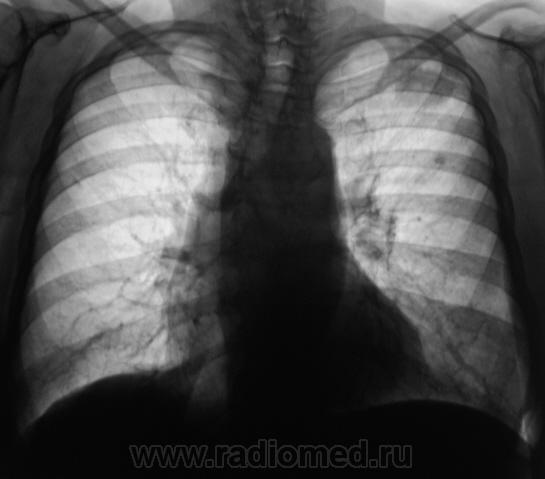

Выставляю томограммы.

11..Vystavlyayu..JPG12..Vystavlyayu.JPG13..Vystavlyayu..JPG

И еще.

14..Vystavlyayu.JPG15..Vystavlyayu.jpg16..Vystavlyayu.JPG17..Vystavlyayu.JPG18..Vystavlyayu..jpg

Слева в S2 похоже на туберкулому (очерченные контуры в отличии от инфильтрата).

Коллеги!!! Спокойный окружающий фон, отсутствие четкого контура, мелкая лучистость по периферии образования, лимфангит к корню, подходящая интенсивность. По-моему здесь классический периферический рак.

Во- первых:я бы сказал, что окружающий фон не совсем спокойный, т.к. за III ребром очаг.Во-вторых периферический рак лёгого (бронха), как правило растёт вдоль длинника бронха- мы этого в данном случае, не видим. В-третьих: при туберкулёзе, то же бывает "дорожка" к корню. Так, что говорить о классическом периферическом раке легкого не стоит.

Выскажу свою точку зрения в "защиту" рака. 1. Одиночный кальцинат за III ребром - это, во-первых, не тот окружающий фон в широком смысле этого слова. А во-вторых, сочетание TBC и c-r очень частое явление (хотя раньше считалось казуистикой). 2. В экспансивную стадию роста c-r растет в сторону наименьшего тканевого сопротивления. Для субплевральной локализации в в/д характерна "приплюснутость", когда длинник фокуса расположен параллельно грудной стенке из-за увеличения давления на наружный и внутренний края образования при дыхании. 3. При TBC "дорожка" к корню чаще бывает нечеткой, смазанной вследствие паравазальной инфильтрации (процесс-то инфекционный). При раке - "чистый" лимфангит. Кроме того - неоднородность структуры (многоузловой рост, возможно и распад).

Итак, если, я правильно понял, то дифференциальную диагностику нужно проводить между периферическим раком легкого и туберкуломой?

Вообще-то дискуссия," что это периферический рак или туберкулома"- подтверждение старой истины:рентгенологически дифференцировать периферический рак и туберкулому практически невозможно.

Да, коллега, Вы совершенно правы. И даже наличие "архива", и даже наличие в окружающей легочной ткани отдельных очажков, не может на все 100 свидетельствовать, что это туберкулома, ибо известны случаи "поглощения", растущей опухолью "старых очагов". Наличие эксцентрического мелкофокусного единичного или множественного распада, также не может свидетельствовать только в пользу рака. Контуры неровные, нечеткие и даже с элементами полицикличности, и даже с мелкой лучистостью, достоверно не могут свидетельствовать ни о раке, ни о туберкуломе. Клиника, также не помощница в данном вопросе, также, как и зачастую специфические пробы. Касательно "дорожки", также вопрос спорный.